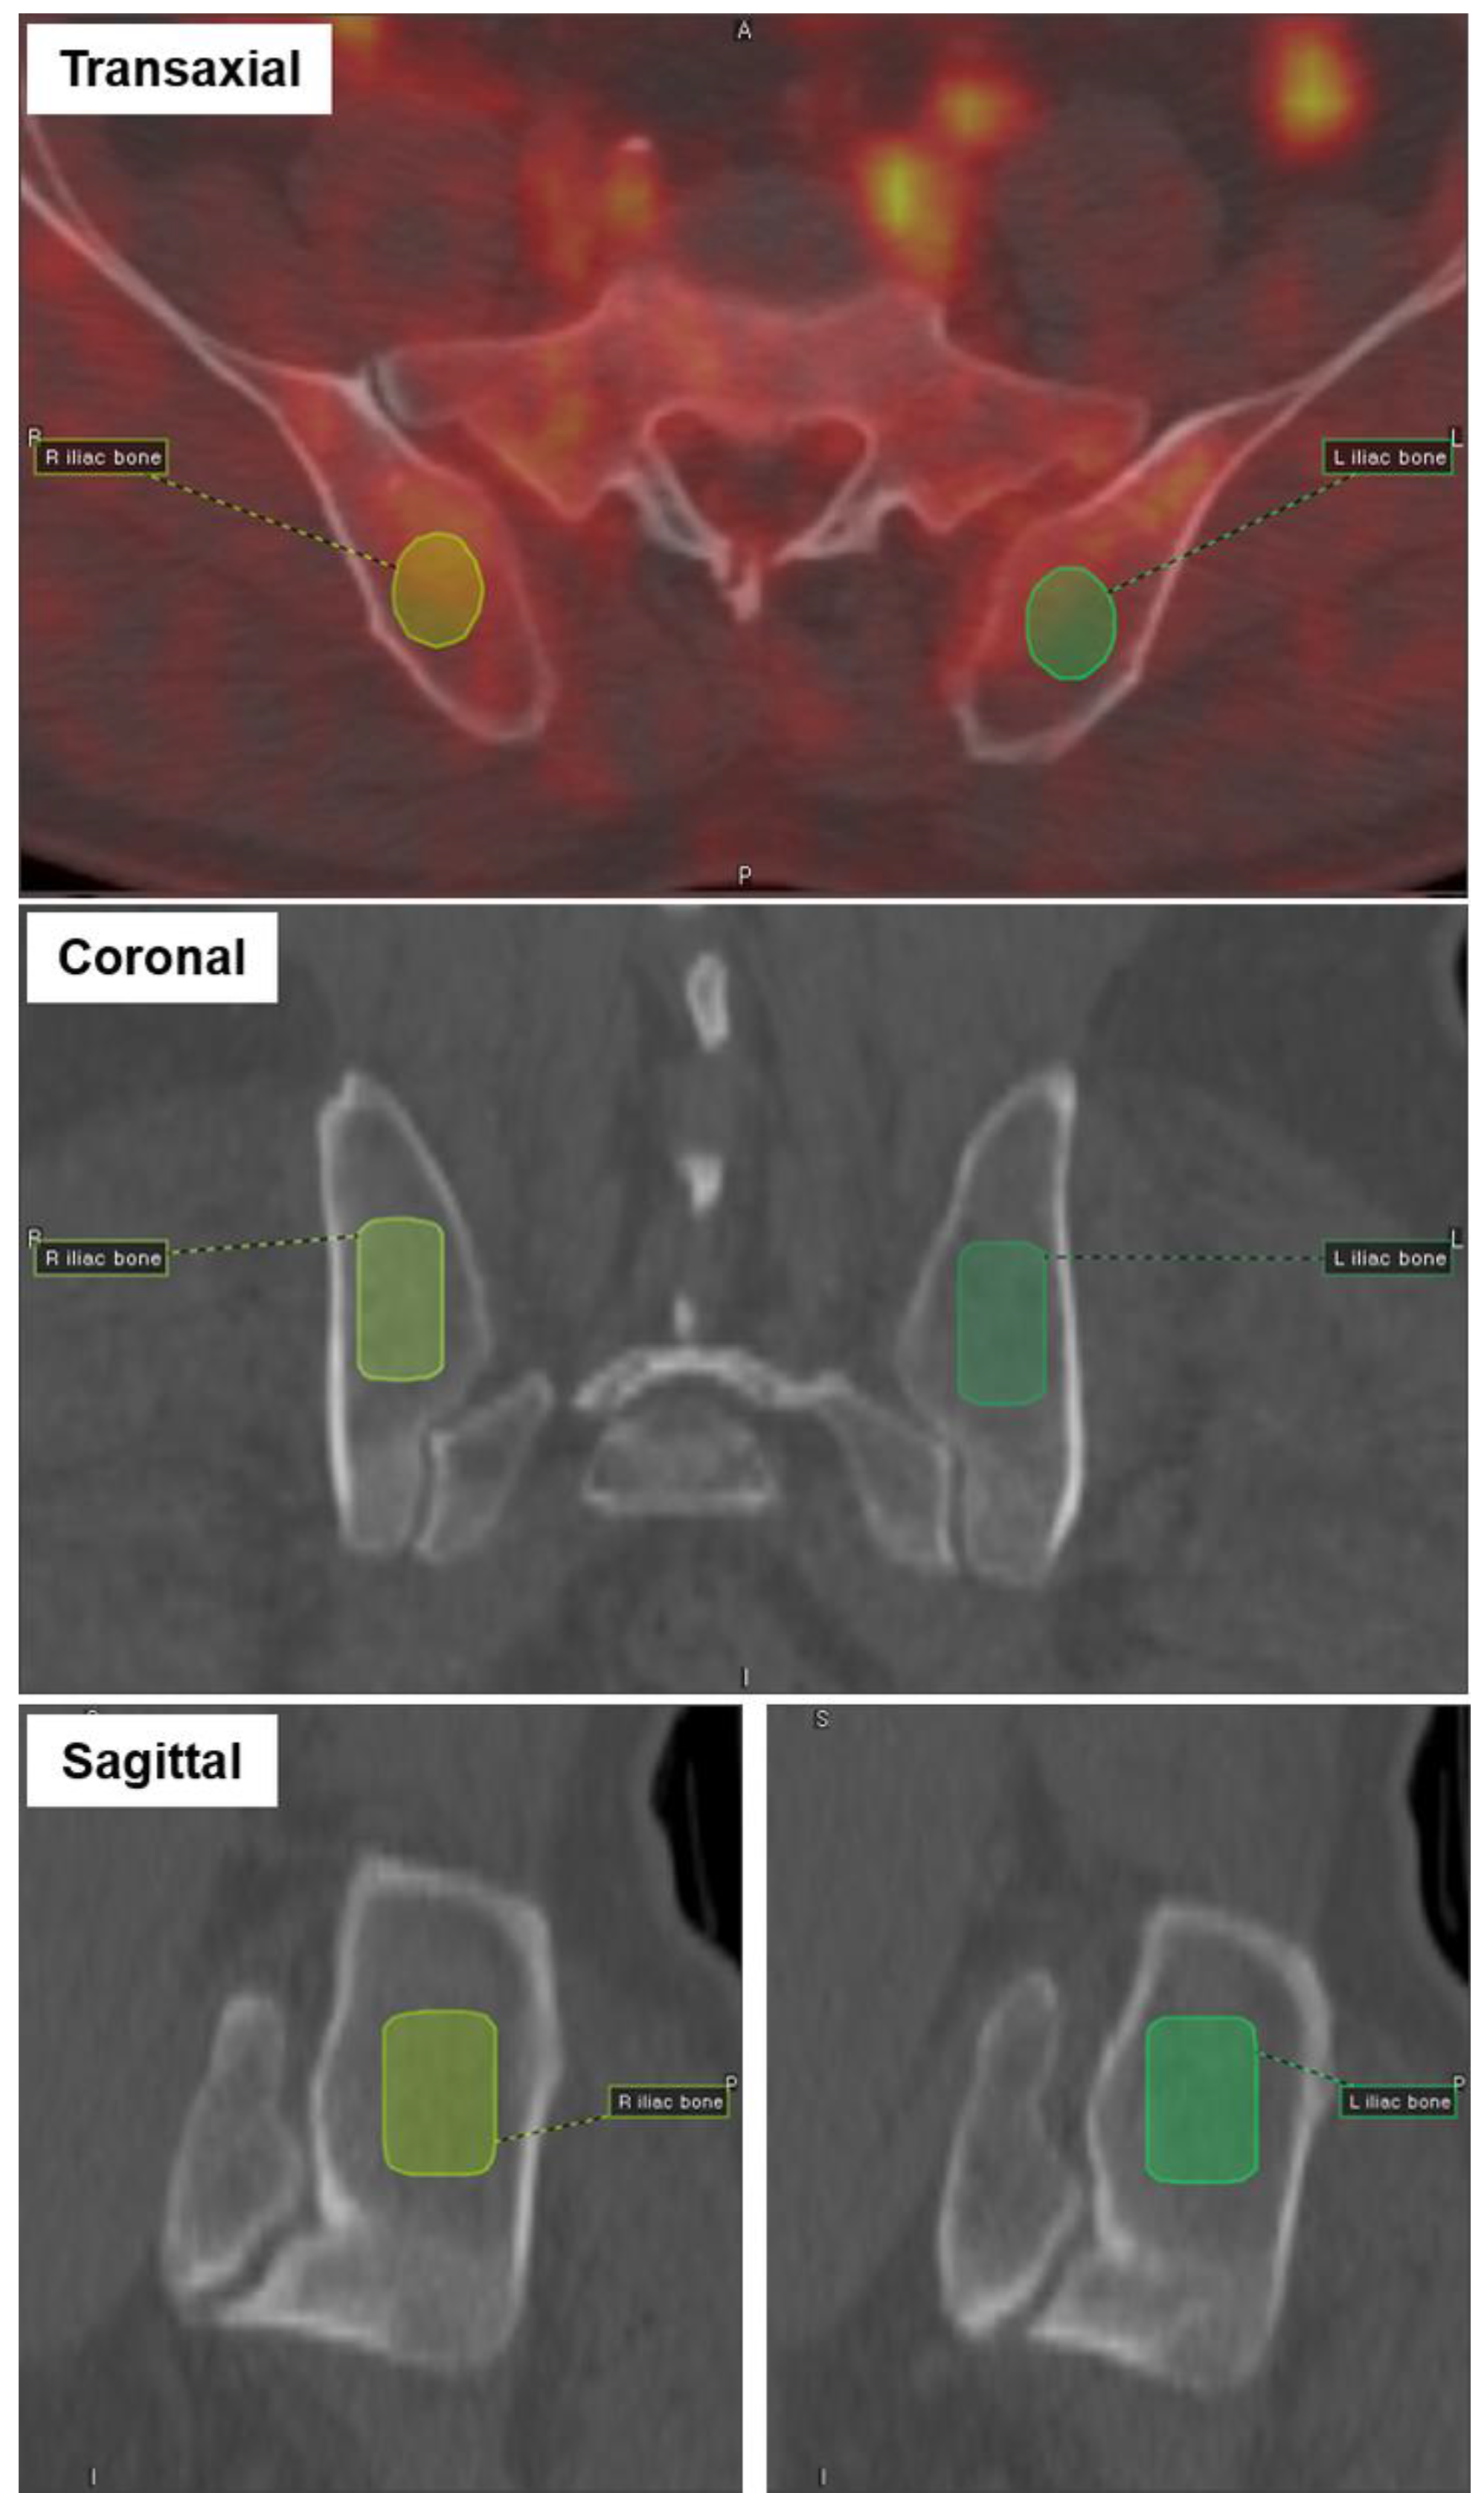

2.4. Extraction of PET Radiomic Features